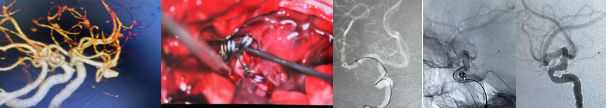

动脉瘤夹闭及介入